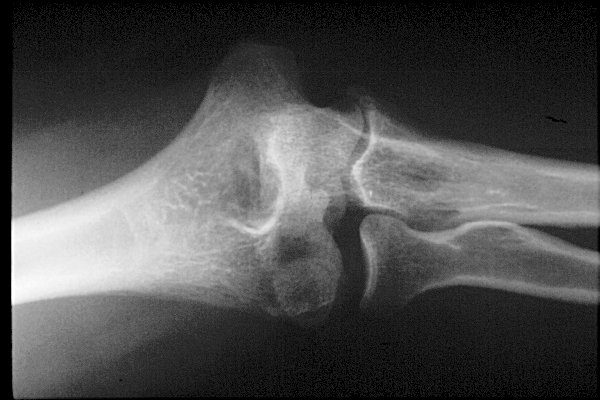

Return to Capitellum Fracture